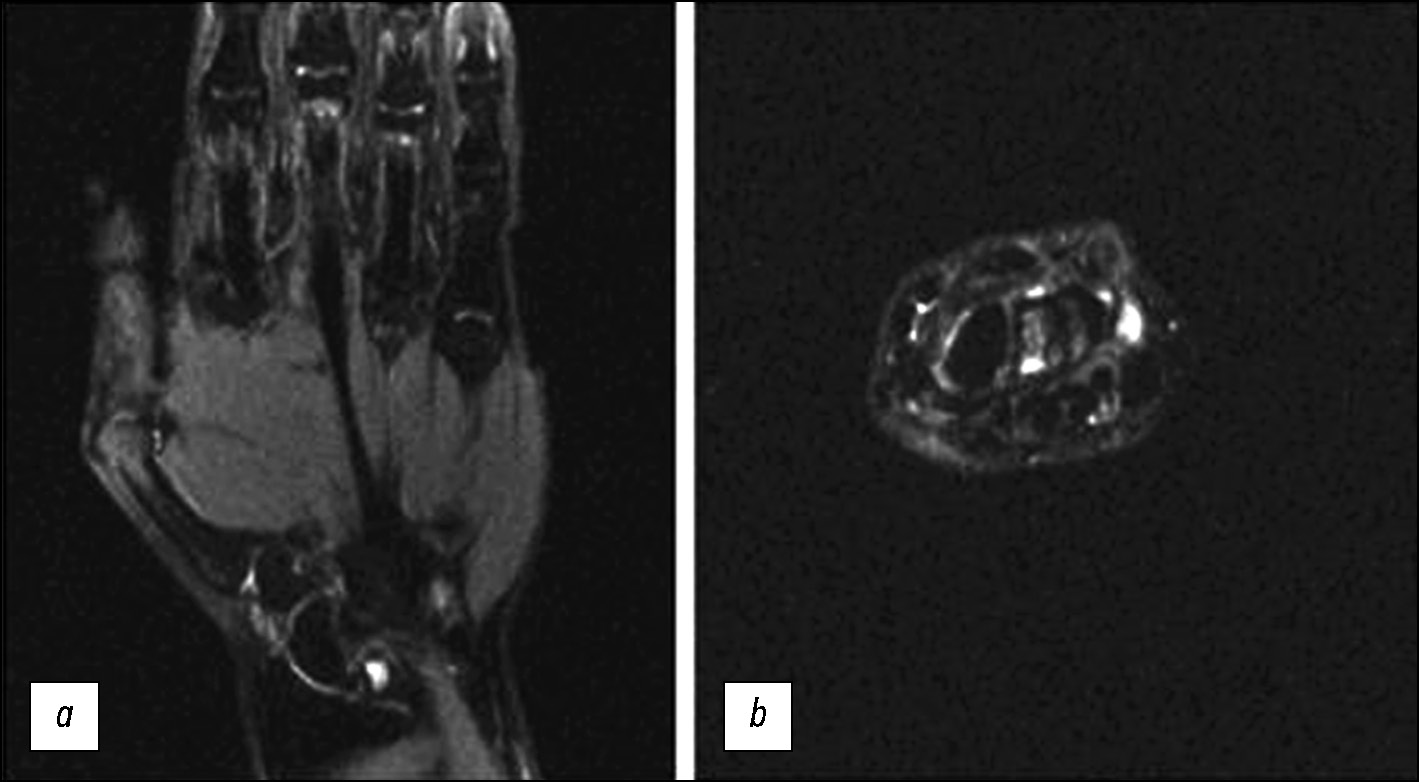

Table 2 presents data comparing head and knee coils. Fig. 4 and 5 display images obtained with the head and knee RF coils. When using the head coil (Fig. 4), the SNR was lower; however, the signal intensity was more evenly distributed, allowing evaluation of the entire hand. However, when the knee coil was used (Fig. 5), the SNR was higher locally, allowing assessment of smaller wrist structures. This was because the knee RF coil was quadrature, not multichannel, and the working field of view was smaller. A survey showed that the head coil was more comfortable for the patient.

Fig. 4. Magnetic resonance imaging of the hand using a head radiofrequency coil, with a splint to immobilize the hand. PD-weighted images with fat suppression; (a) coronal plane; (b) axial plane.

Fig. 5. Magnetic resonance imaging of the hand using a knee radiofrequency coil, with a splint to immobilize the hand. PD-weighted images with fat suppression; (a) coronal plane; (b) axial plane.